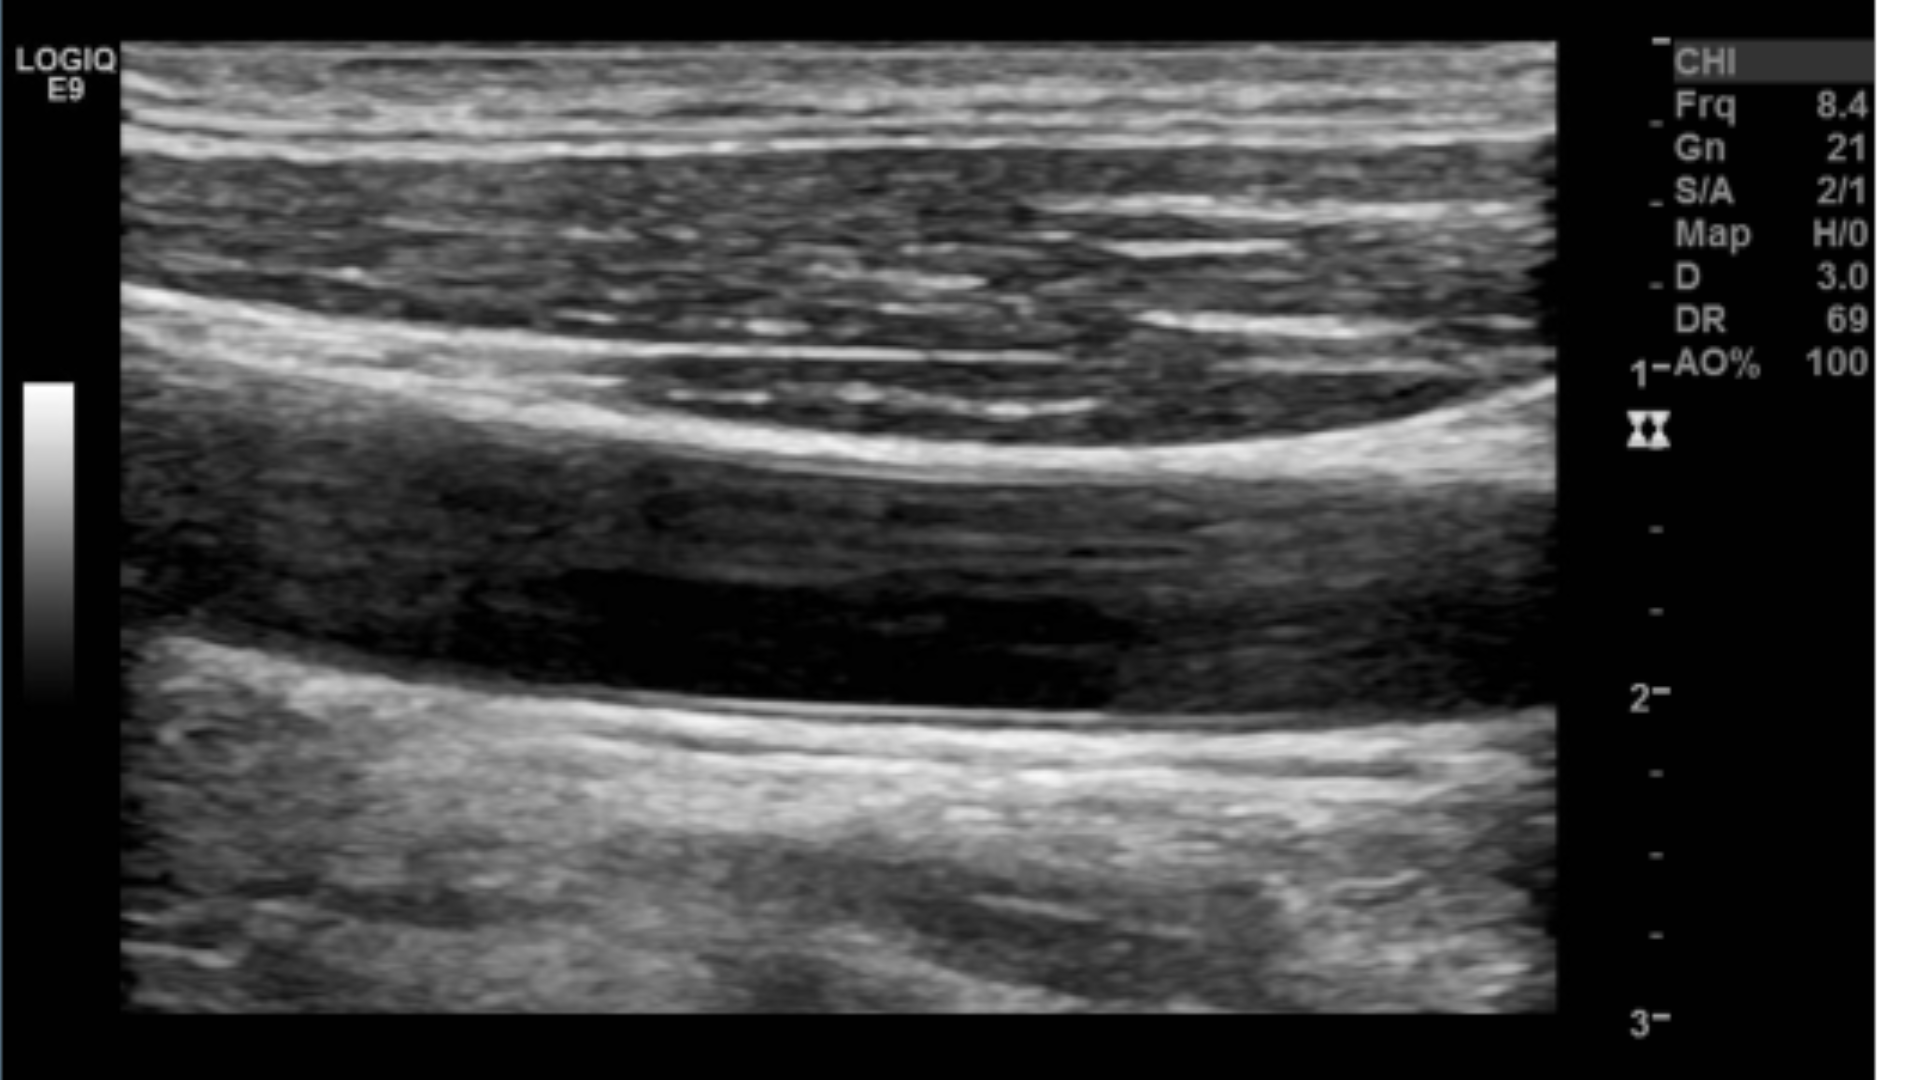

TGC’s not optimized

TGC’s optimized